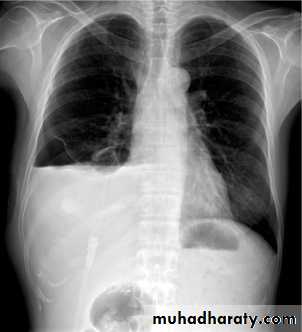

Pleural effusion

Pleural effusion tends to be used as a catch-all term denoting a collection of fluid within the pleural space. This can be further divided into exudates and transudates depending on the biochemical analysis of aspirated pleural fluid. Essentially it represents any pathological process which overwhelms the pleura's ability to reabsorb fluid.Radiographic appearances

Plain radiographChest radiographs are the most commonly used examination to assess for presence of a pleural effusion, however it should be noted that on a routine erect chest x-ray as much as 250-600 ml of fluid is required before it becomes evident 6. A lateral decubitus film is most sensitive, able to identify even a small amount of fluid. At the other extreme, supine films can mask large quantities of fluid.

CXR (erect)

Both PA and AP erect films are insensitive to small amounts of fluid. Features include:

blunting of the costophrenic angle

blunting of the cardiophrenic angle

fluid within the horizontal or oblique fissures

eventually a meniscus will be seen, on frontal films seen laterally and gently sloping medially (note: